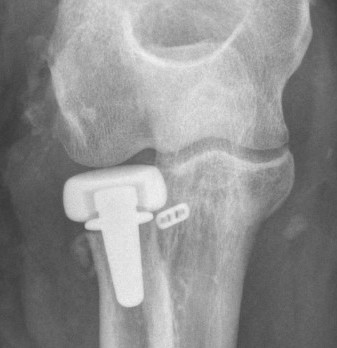

rh orif Radial Head Replacement Lateral

Type II / Reconstructable radial head Type III / Radial head arthroplasty

Lateral / Kocher / Kaplan / EDC split approach

- radial head replacement

- LCL +/- common extensor origin repair

Radial head replacement with lag screw fixation of Type II coronoid